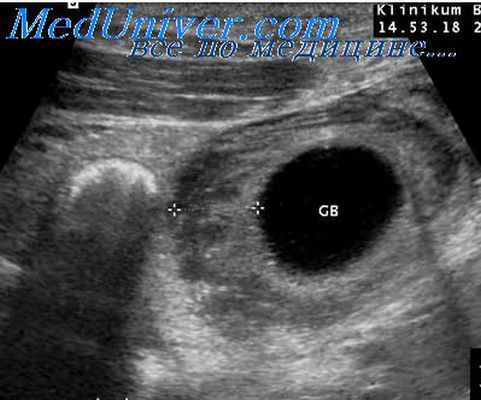

- УЗИ. При ультразвуковой диагностике исследуют брюшную полость, желчные пути, печень. Исследование направлено на выявление патологических расширений желчных протоков, очаговых и структурных изменений печени.